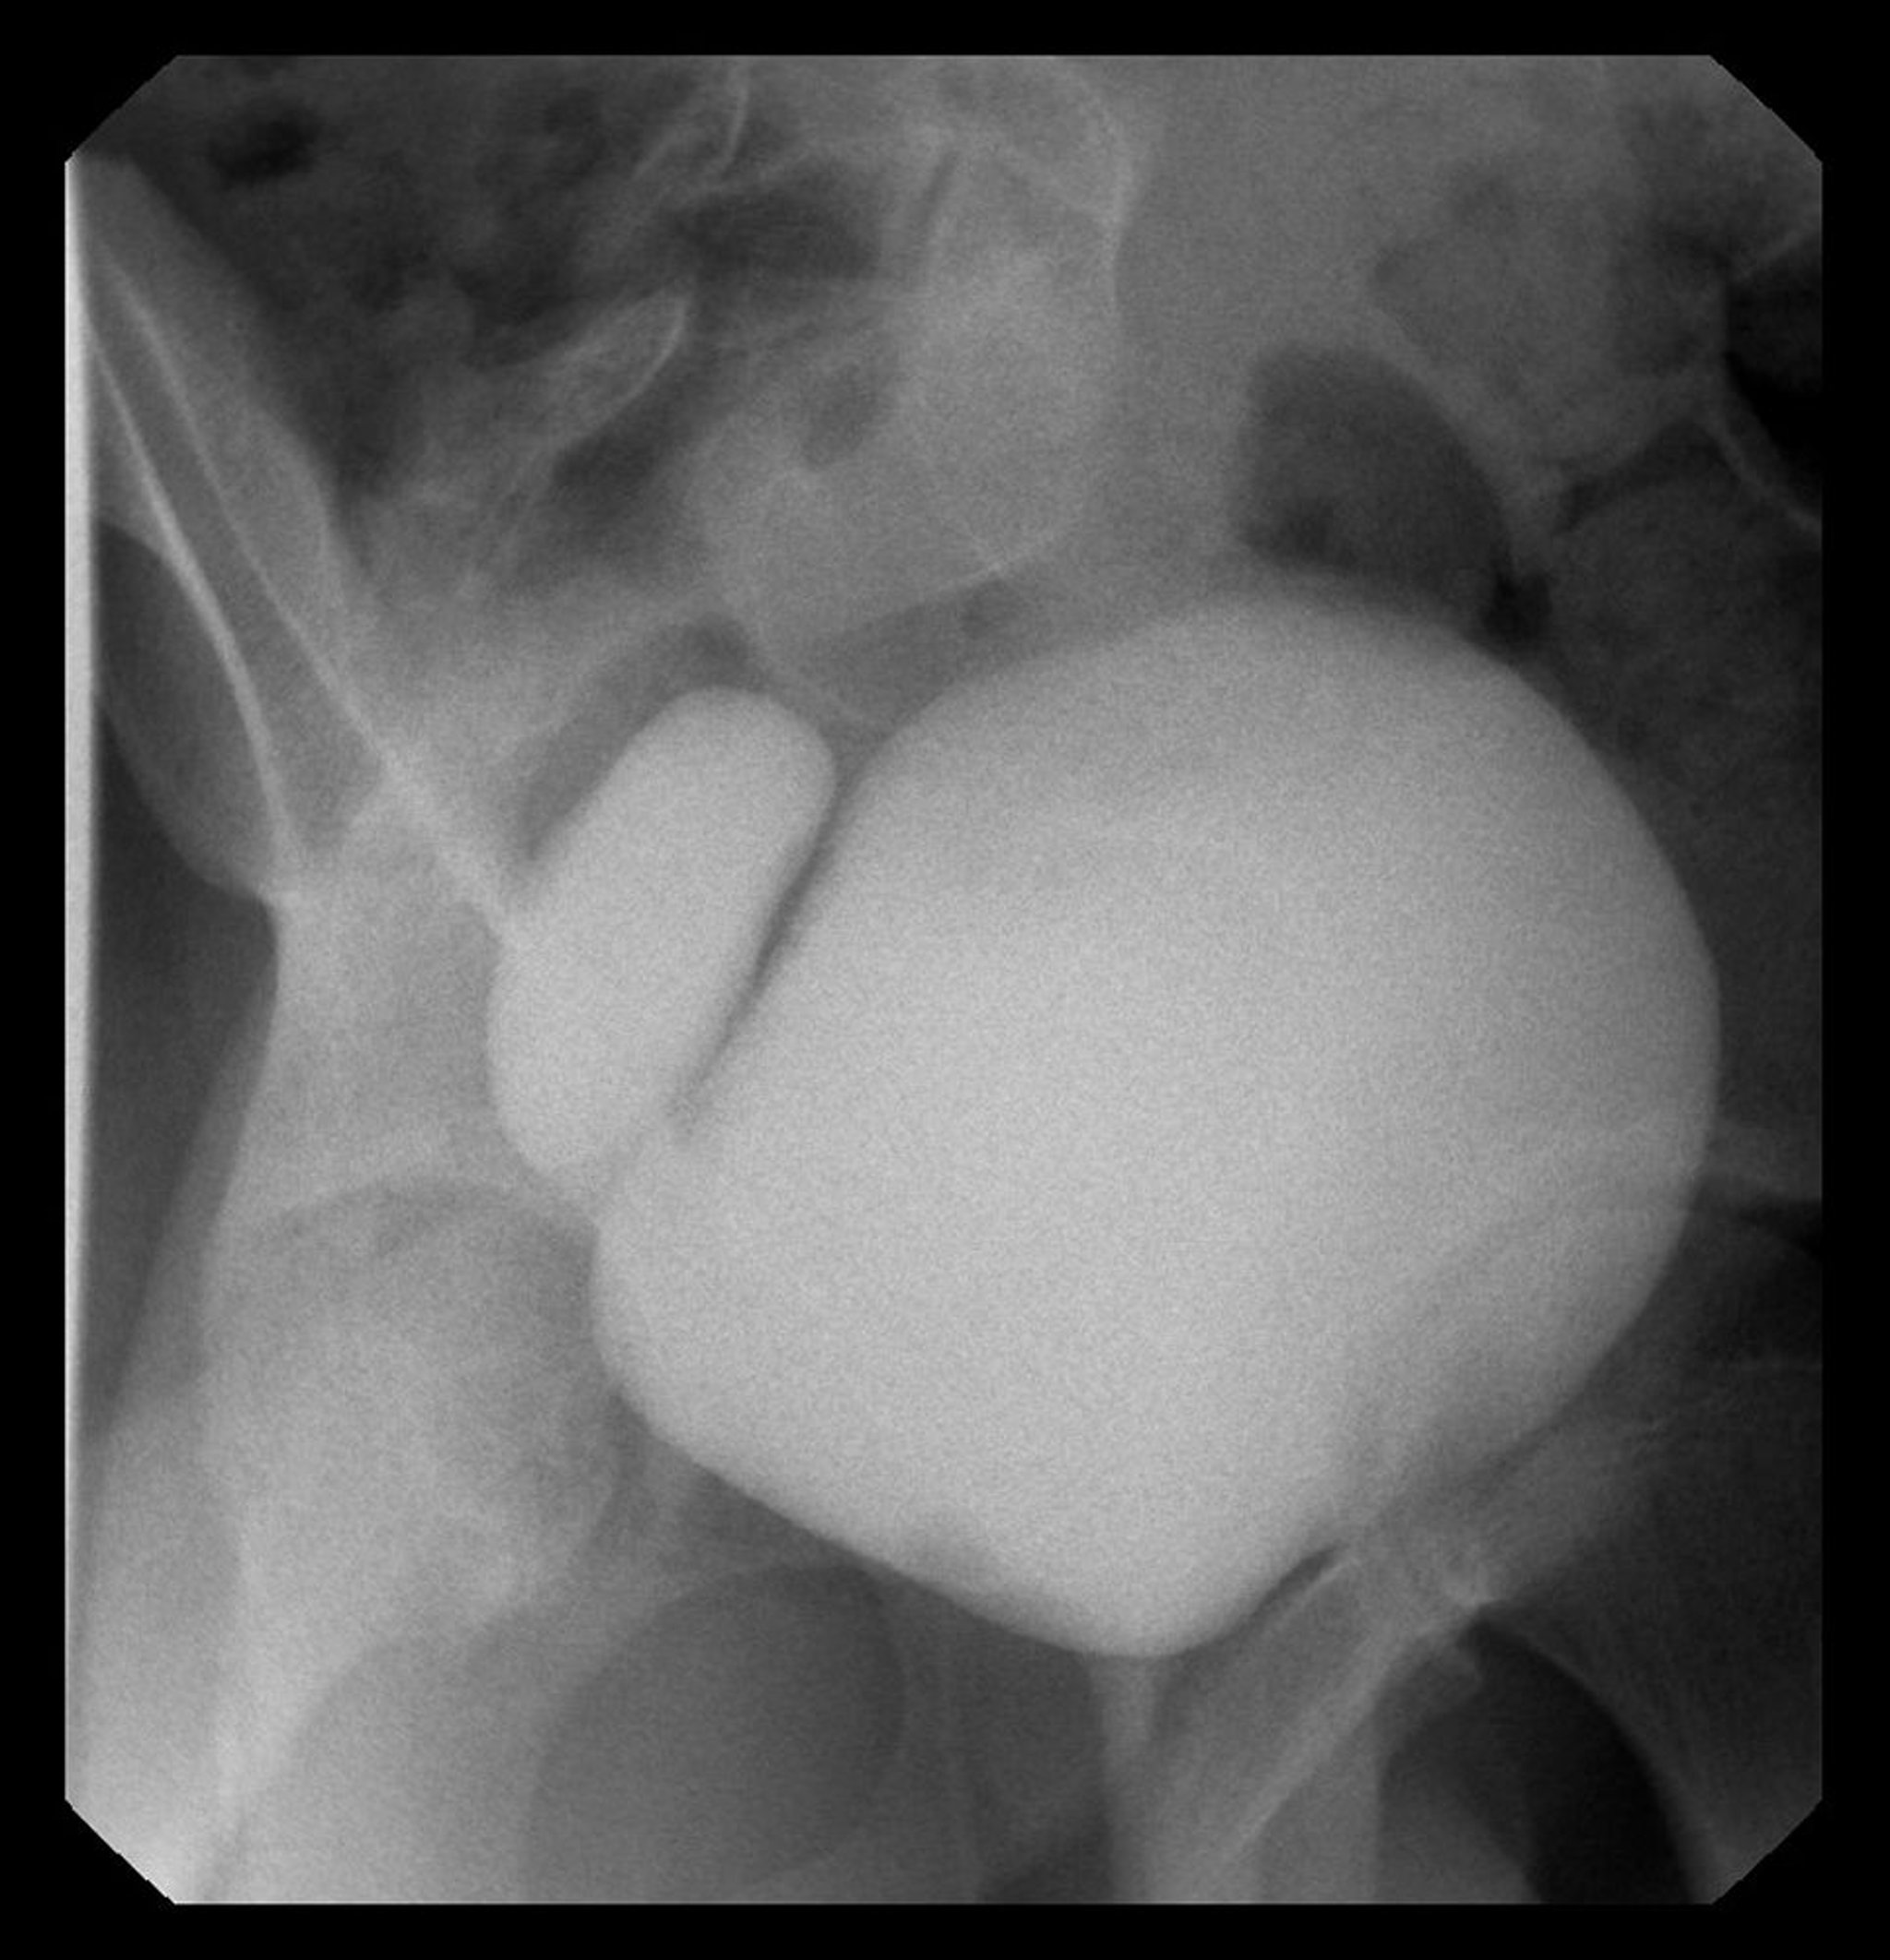

Hình ảnh này cho thấy chụp X-quang bàng quang có túi thừa bàng quang bên phải.